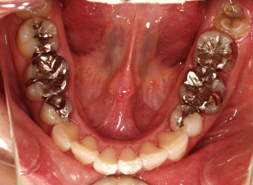

下顎から見た口中の写真

ただ単純に白い歯にすればきれいに見えるかもしれませんが、その歯が長くきれいに保つためには様々な問題をクリアしていかなければなりません。私達ができること、それは、その基礎となる環境を整えることだと考えています。(歯の神経の治療に限らず歯周病、かみ合わせ、適合精度や審美的観点から技工物を製作できる技工士と付き合うことなどなど。)御自身の日々のお手入れ(歯磨きなど)や、クリニックに定期的に御来院いただきメンテナンス管理させていただくことで、この状態を少しでも長く維持できることを心より望み、心がけています。

虫歯になっている歯はもちろん、この患者様は銀歯をすべて白い歯で治療されています。